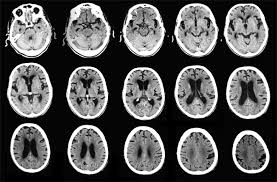

Tomografía axial computerizada o TAC

Se utiliza la técnica de los rayos X combinada con el poder de la tecnología informática para tratar muchos datos.

El TAC es una técnica que viene a ser como un conjunto de radiografías de un cuerpo realizadas a varios milímetros de distancia unas de otras, de forma que genera imágenes de segmentos del cuerpo; se obtienen imágenes como si se hubiese cortado el cuerpo en láminas.

Con estas imágenes se puede conocer con exactitud anomalías anatómicas sin necesidad de penetrar en el cuerpo; se conoce, por ejemplo, la extensión de los tumores, para así plantear los tratamientos.